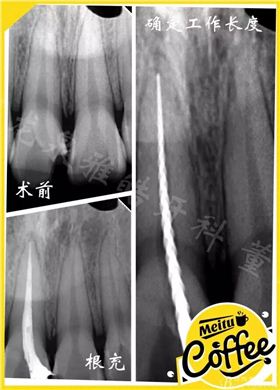

常規(guī)根管治療

開(kāi)髓孔正常應(yīng)該設(shè)計(jì)到鄂側(cè),后來(lái)考慮到使用鎳鈦器械 柔韌性比較好(K3還是比較硬的)

若不影響直線通道的建立 擴(kuò)銼針在根管內(nèi)的正常運(yùn)行 就不去破壞舌側(cè)窩形態(tài)了。

配合超聲蕩洗 非常順利的預(yù)備好根管

超聲蕩洗每次45秒

根管沖洗 一點(diǎn)要做好